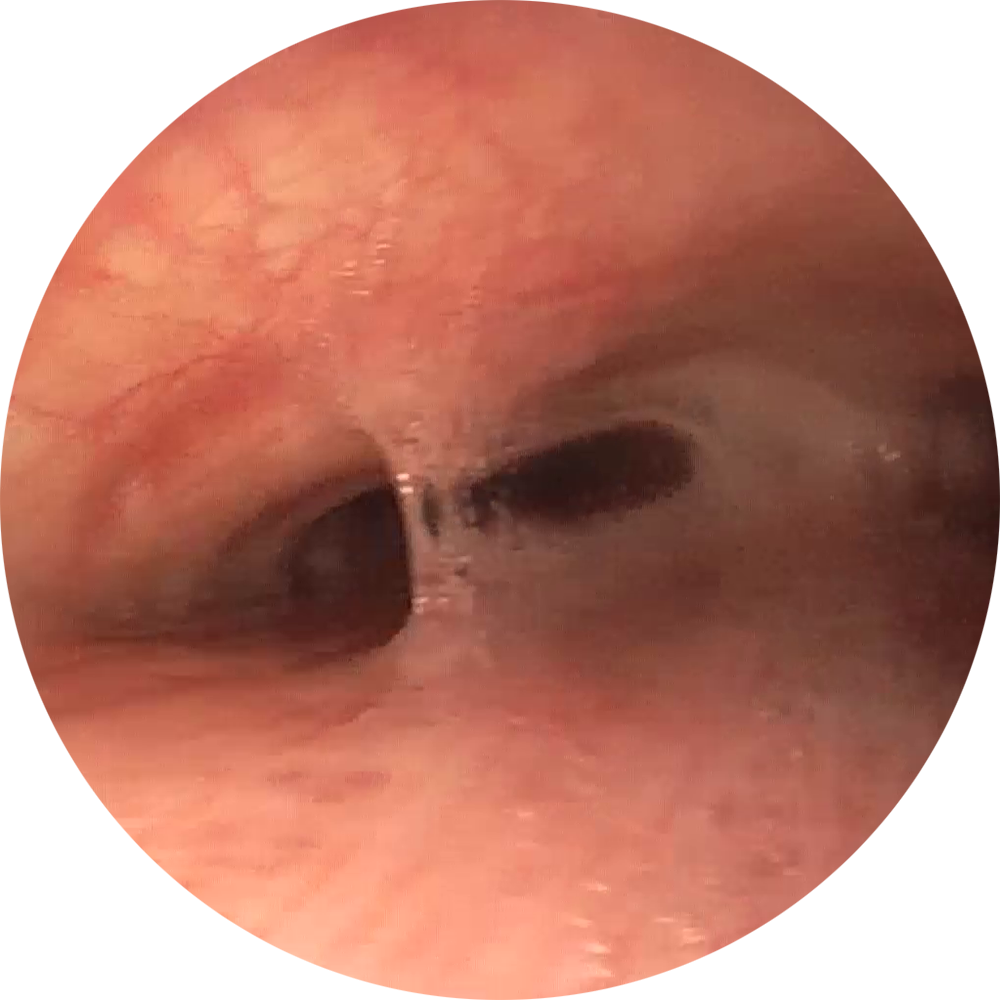

Erfolgreiche Implantation eines NOVATECH® 3D Stent bei einem Patienten mit Bronchomalazie im rechten Bronchus.

Bilder freundlicherweise zur Verfügung gestellt

von PD Dr. Daniel Franzen, Zürich.